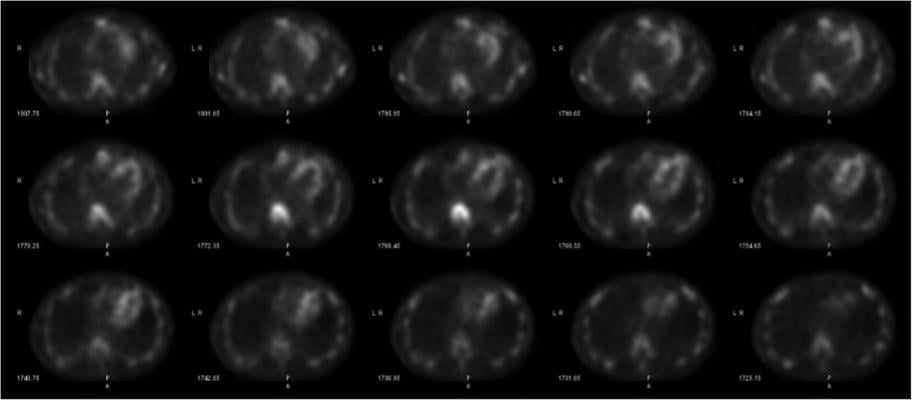

Cardiac amyloidosis is emerging as an underdiagnosed cause of heart failure and mortality characterized by the deposition of amyloid fibrils (misfolded protein deposits) into myocardial tissue. An ideal non-invasive diagnostic method would identify cardiac involvement in amyloidosis and would also confirm the etiologic subtype. No existing diagnostic tools can provide this information individually, necessitating a multimodality cardiac imaging approach.